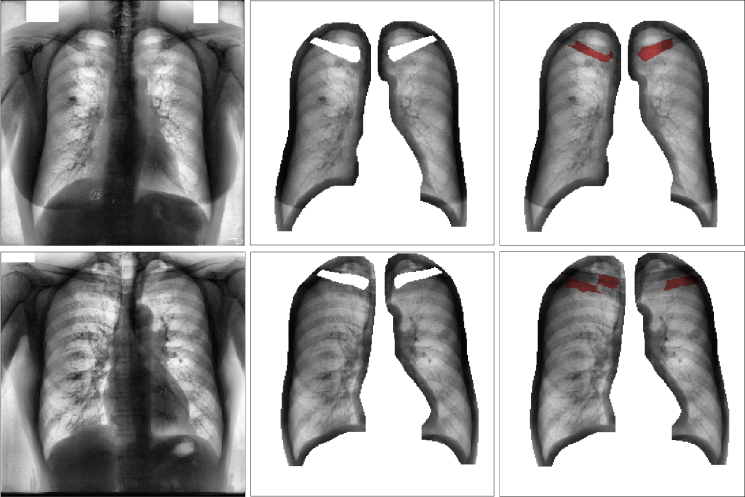

Refer to caption

Figure 1: Multi-class segmentation process: from input chest CXR to three masks of lungs, clavicles and heart